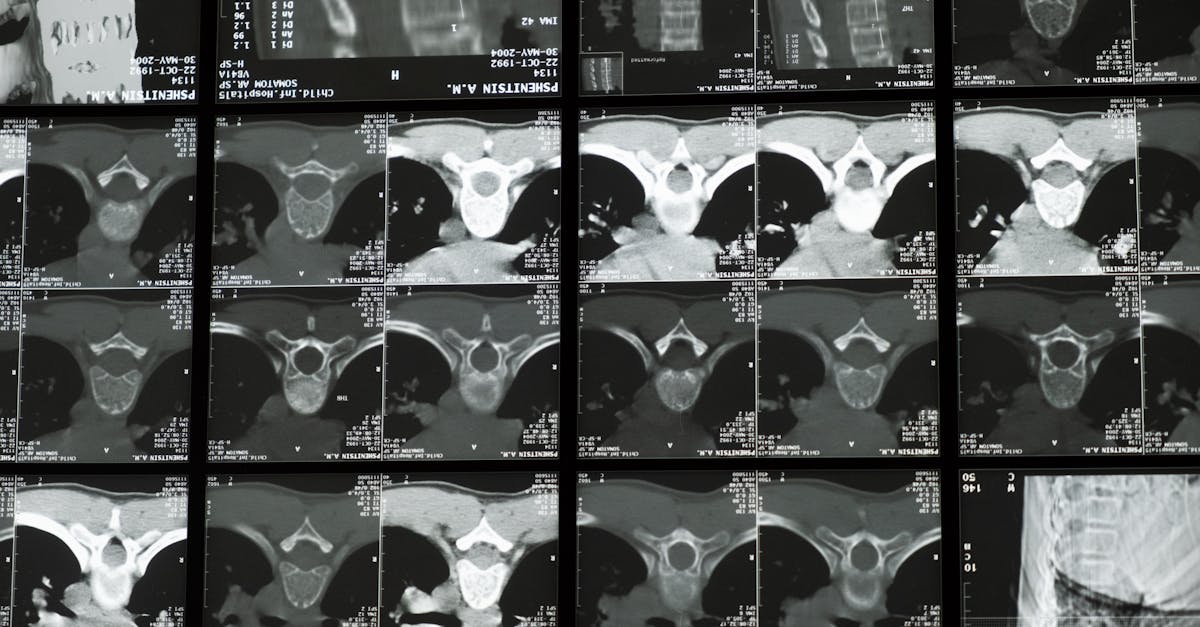

Brachialgia refers to pain that radiates from the neck to the arm. It often occurs due to herniated discs, narrowing in the nerve foramens, or problems at the level of the vertebrae. These conditions can lead to nerve compression, resulting in pain, numbness, and muscle weakness. Brachialgia can significantly disrupt quality of life, making daily activities challenging.

Brachialgia manifests as pain radiating from the neck to the arm, often caused by vertebral imbalances. This condition is often related to herniated discs that put pressure on the cervical nerves. Symptoms can range from mild pain to intense tingling sensations, potentially leading to an inability to perform certain daily tasks. Understanding the causes of brachialgia is crucial for choosing the most appropriate treatment.

Spinal decompression uses biomechanical principles to relieve pressure on the nerves and intervertebral discs. This method involves gentle, controlled traction that helps widen the space between the vertebrae. By relieving tension on the spine, it promotes better blood circulation and creates an environment conducive to tissue healing. This can lead to a reduction in symptoms associated with brachialgia.

The spinal decompression technique is based on physical and biomechanical principles aimed at widening the space between the vertebrae. This action reduces the pressure on the intervertebral discs, facilitating their regeneration and thereby reducing compression on the nerves. By using special traction tables, the practitioner can adjust the forces applied, which creates a beneficial traction effect on the spine.